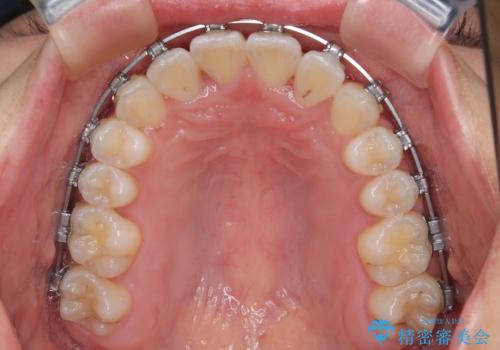

前歯のクロスバイト 裏側に隠れた歯をワイヤー装置で短期間治療

- 矯正装置

- メタルブラケット

- 上顎前歯のクロスバイトを気にして来院された患者様です。

ワイヤー矯正でもマウスピース矯正でも対応可能でしたが、マウスピースによる自己管理に一切の自信がないとのことで、ワイヤー装置にて矯正治療を行うこととしました。

装置の外見を気にしていましたが、短期間で治療を終えることができるだろうと伝えると、安価であるメタルブラケットを選択されました。

想定通り、1年強で綺麗に仕上げることができました。